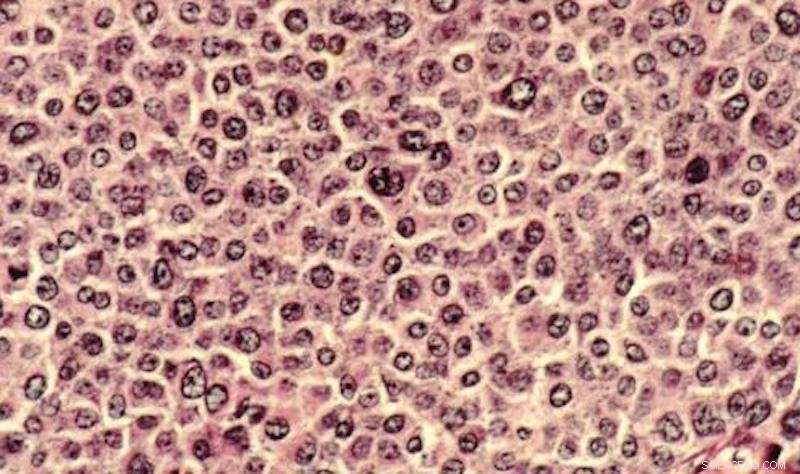

Cancer cells have traditionally been studied in petri dishes and on microscope slides. Researchers have now developed a 3-D model to analyze the complexities of cancer cells in an environment that more closely mimics the human body. Credit: Dr. Cecil Fox, Public Domain

Although cell analysis traditionally occurs in a plastic petri dish, the research team created a 3-D model that more accurately reflects the physiological conditions of an organism. With this model, scientists can uncover and analyze the complexities of cancer cells in an environment that more closely mimics the human body.